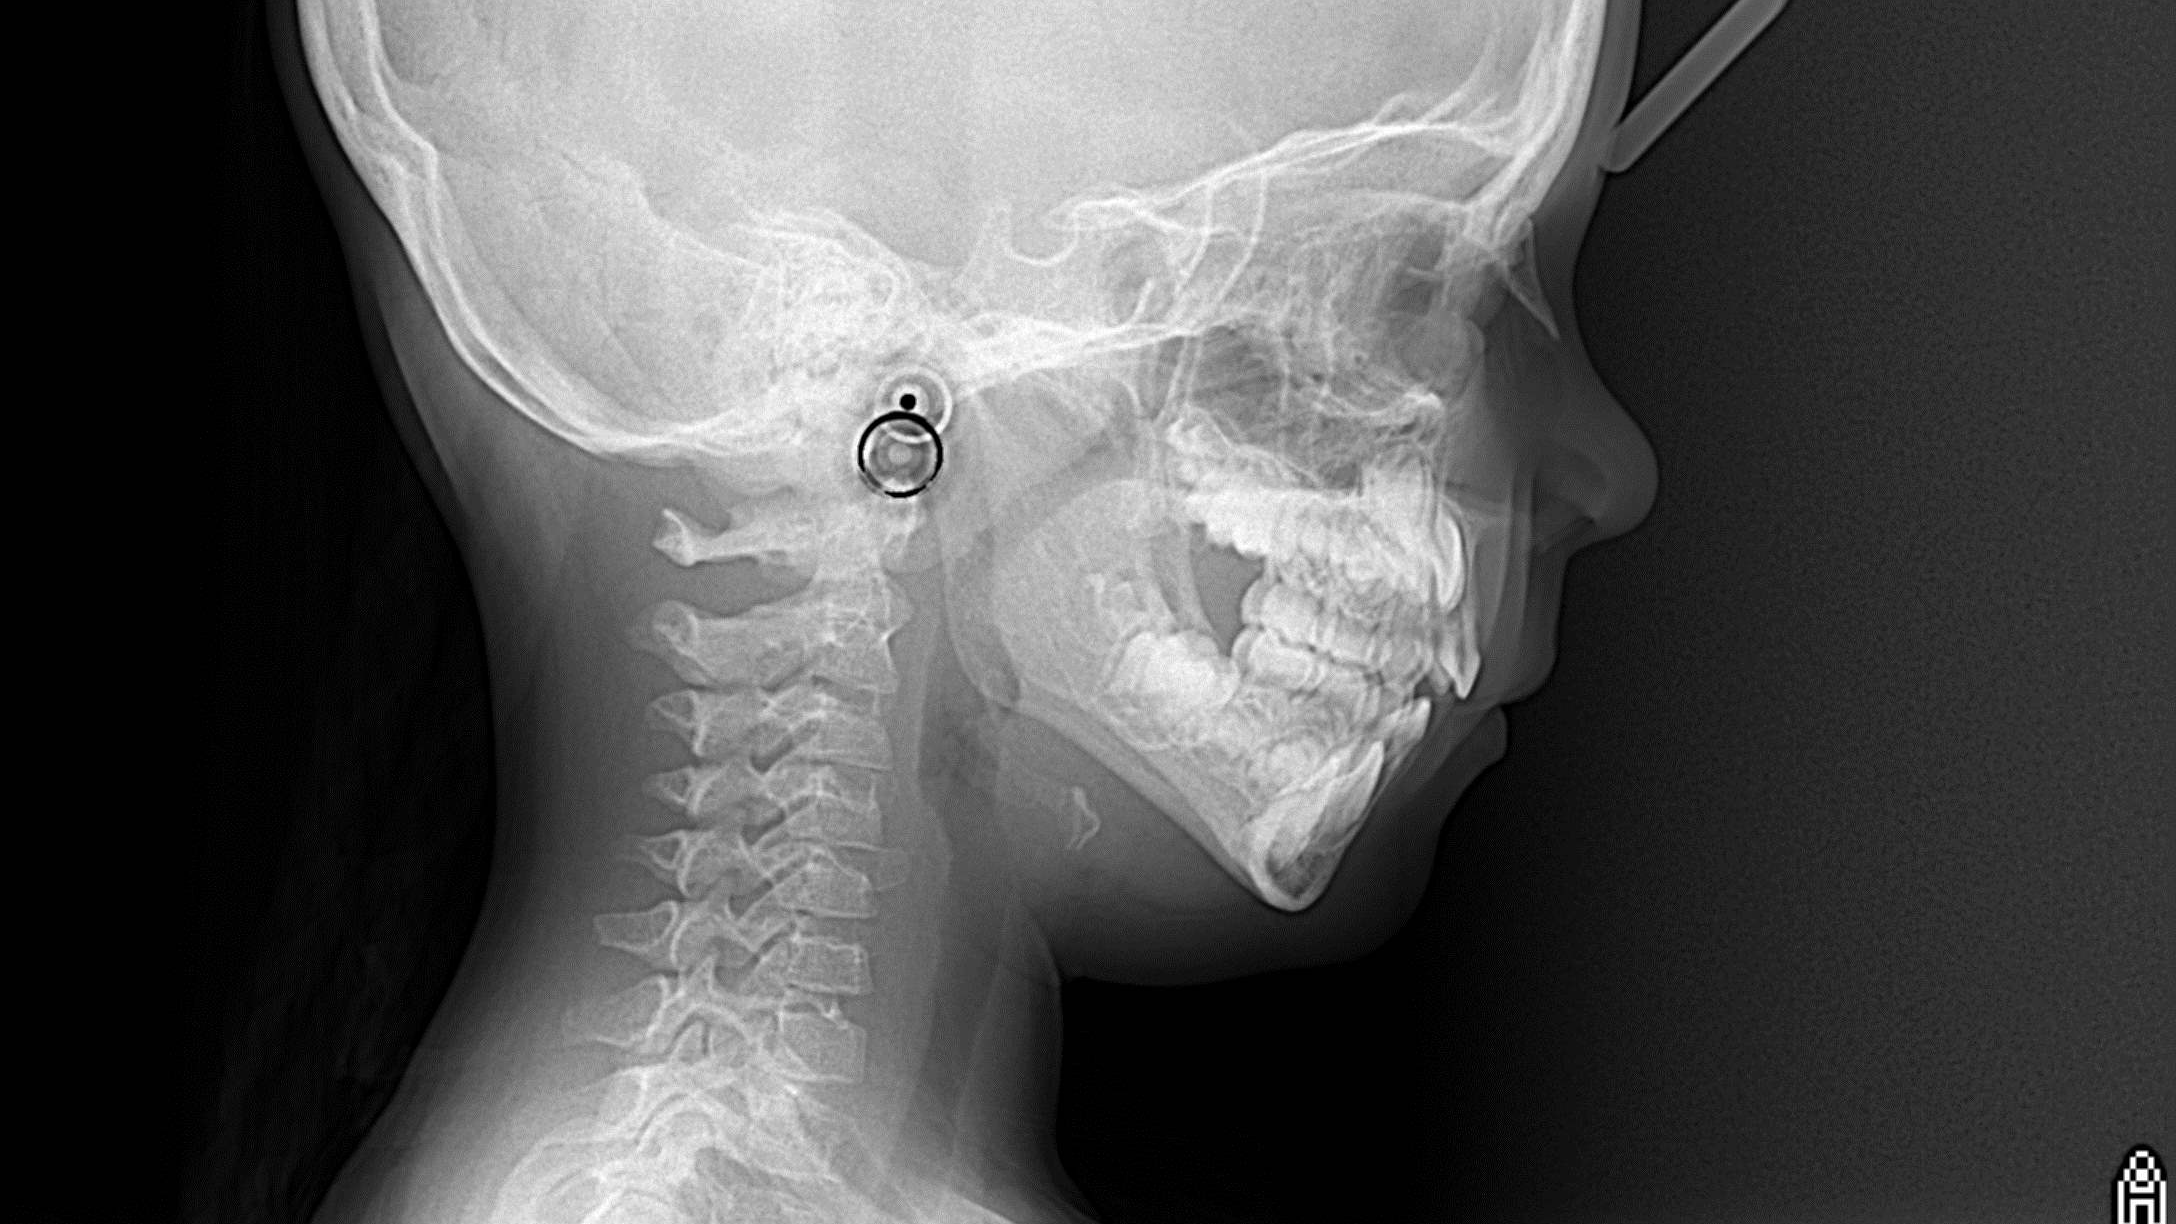

bilan début et en cours de traitement

bilan des radiographies début et en cours de traitement